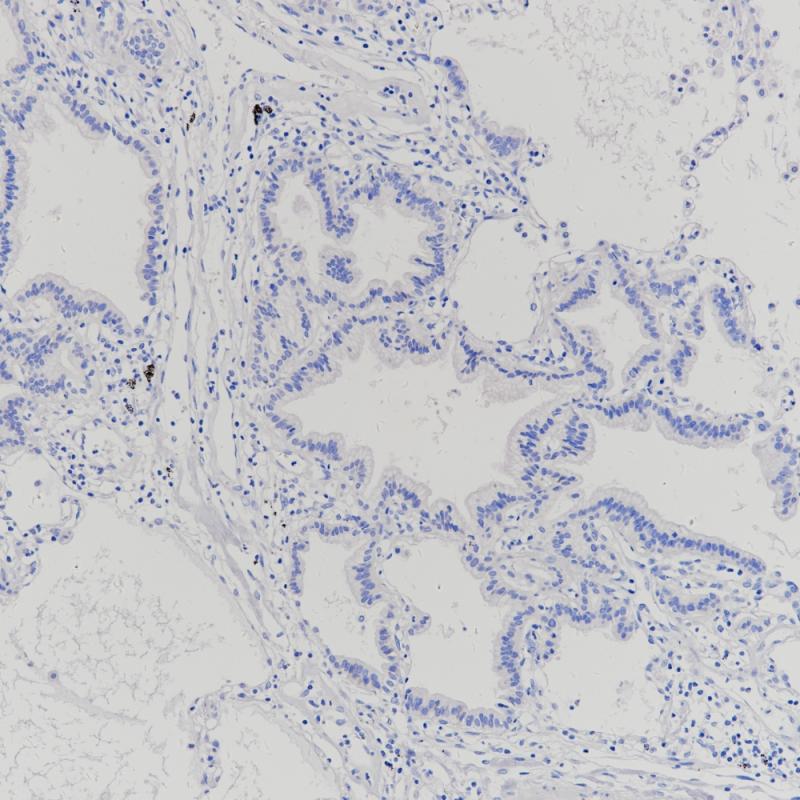

肺Claudin 18.2(BP6249)染色

肺腺癌Claudin 18.2(BP6249)染色